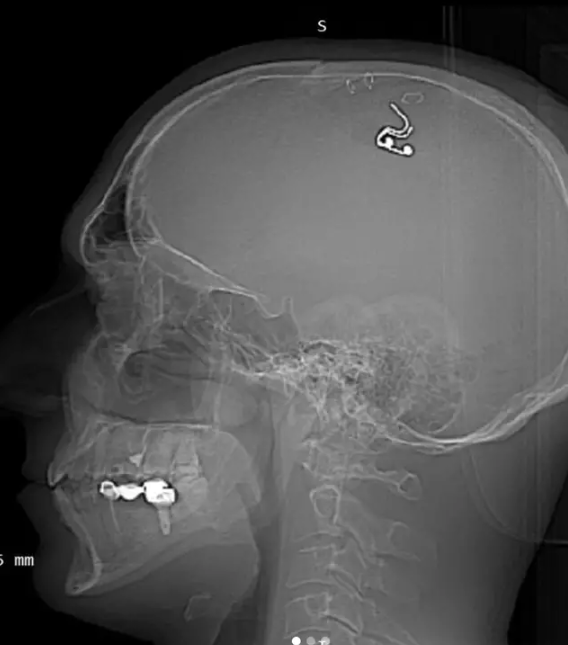

Der Mann bohrte mit einem Bohrer seinen Schädel auf und implantierte den Chip in seinem Gehirn.

Obwohl er sich dafür entschied, sein eigenes Gehirn zu operieren, erzählte Raduga der Daily Mail, dass er keine neurochirurgischen Qualifikationen hat und dass er Teile seiner Haut mit Büroklammern zusammenhielt, während er mit einem Bohrer, den er in einem Baumarkt gefunden hatte, an seinem Schädel arbeitete, um die Elektrode zu implantieren.

Fünf Wochen nach der Implantation des Chips entfernte Raduga diesen wieder, aber es besteht die Sorge, dass er bereits durch die Durchführung des Eingriffs langfristige Schäden davontragen könnte.